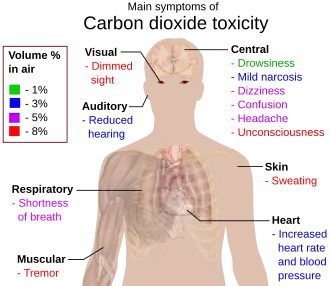

Toxicity

In humans, exposure to CO2 at concentrations greater than 5% causes the development of hypercapnia and respiratory acidosis.[47] Concentrations of 7% to 10% (70,000 to 100,000 ppm) may cause suffocation, even in the presence of sufficient oxygen, manifesting as dizziness, headache, visual and hearing dysfunction, and unconsciousness within a few minutes to an hour.[48] Concentrations of more than 10% may cause convulsions, coma, and death. CO2 levels of more than 30% act rapidly leading to loss of consciousness in seconds.[47]

Below 1%

There are few studies of the health effects of long-term continuous CO2 exposure on humans and animals at levels below 1%. Occupational CO2 exposure limits have been set in the United States at 0.5% (5000 ppm) for an eight-hour period.[54] At this CO2 concentration, International Space Station crew experienced headaches, lethargy, mental slowness, emotional irritation, and sleep disruption.[55] Studies in animals at 0.5% CO2 have demonstrated kidney calcification and bone loss after eight weeks of exposure.[56] A study of humans exposed in 2.5 hour sessions demonstrated significant negative effects on cognitive abilities at concentrations as low as 0.1% (1000 ppm) CO2 likely due to CO2 induced increases in cerebral blood flow.[52] Another study observed a decline in basic activity level and information usage at 1000 ppm, when compared to 500 ppm.[53]